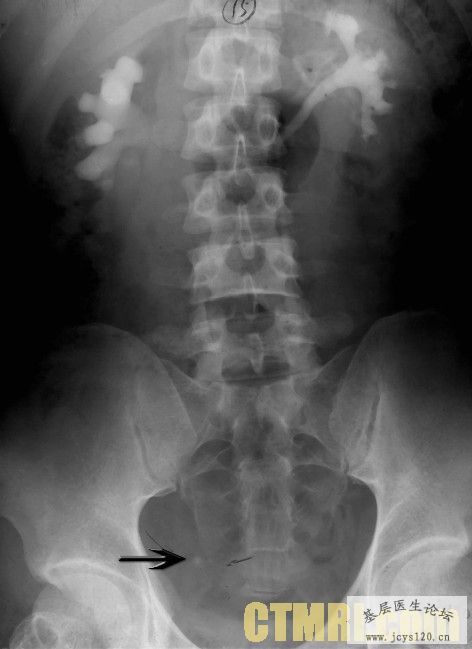

• 男43,主诉阵发性腹痛10余天。 于10余天前无明确诱因出现中腹部阵发性疼痛,无放射性疼痛,无发热,二便正常,无消瘦 查体;脐左侧一个长5宽3厘米的肿块压痛明显,无反跳痛,扣程浊音。 此肿块为什么那,问问大家 ...  阅读全文>